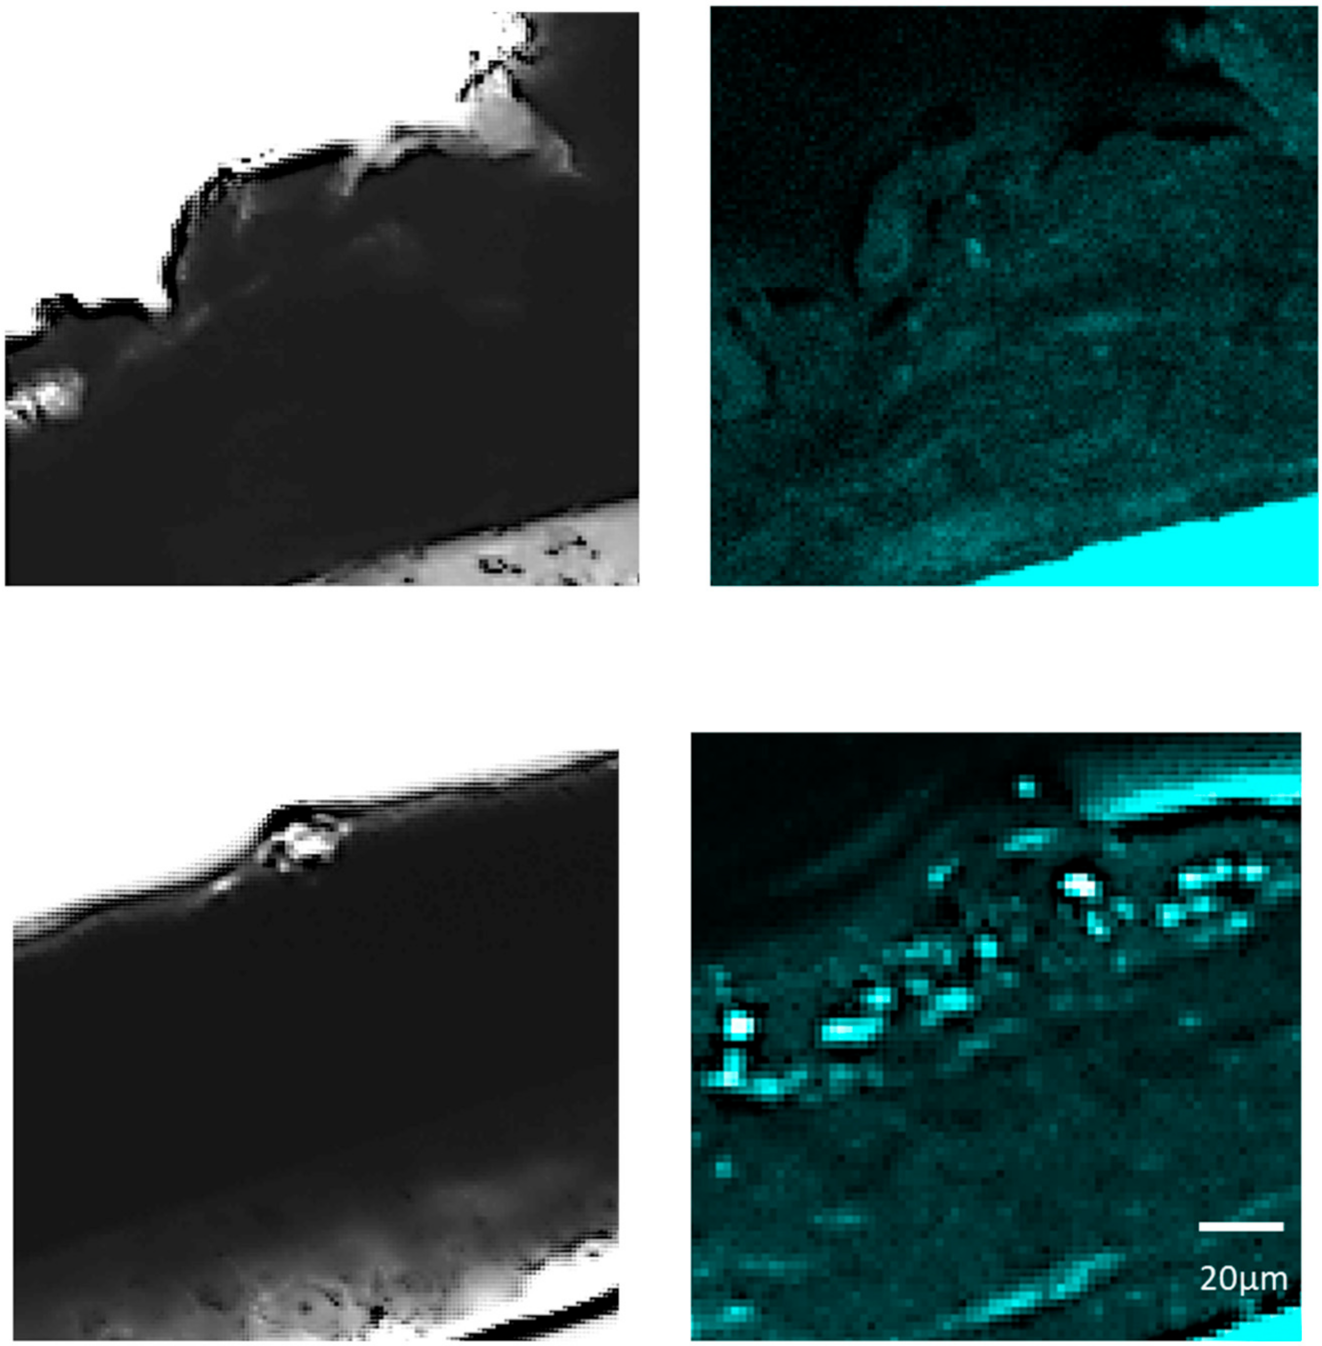

Staining for CASP14 was performed using Ac-WEHD-pNA (Ac-Trp-Glu-His-Asp-pNA) as a substrate in tissue sections applied with LMHA or solvent (control) in which an increase in immunoreactive FLG was observed. FastBlue was used as the staining reagent, and the images were observed at 359/461 nm using an inverted confocal laser scanning microscope. Bright field and fluorescence images were taken at 100× magnification and the areas where fluorescence was observed were magnified. Higher fluorescence intensity was observed in the stratum corneum to stratum granulosum in the 3D epidermis model applied with LMHA compared to the control (Figure 4).

Figure 4.

Fluorescence staining for CASP14 activity in the 3D epidermis models with topically applied LMHA or solvent (control). (top) Solvent-applied 3D epidermis model (control) (left: bright field, right: fluorescence), (bottom) LMHA-applied 3D epidermis model (left: bright field, right: fluorescence).